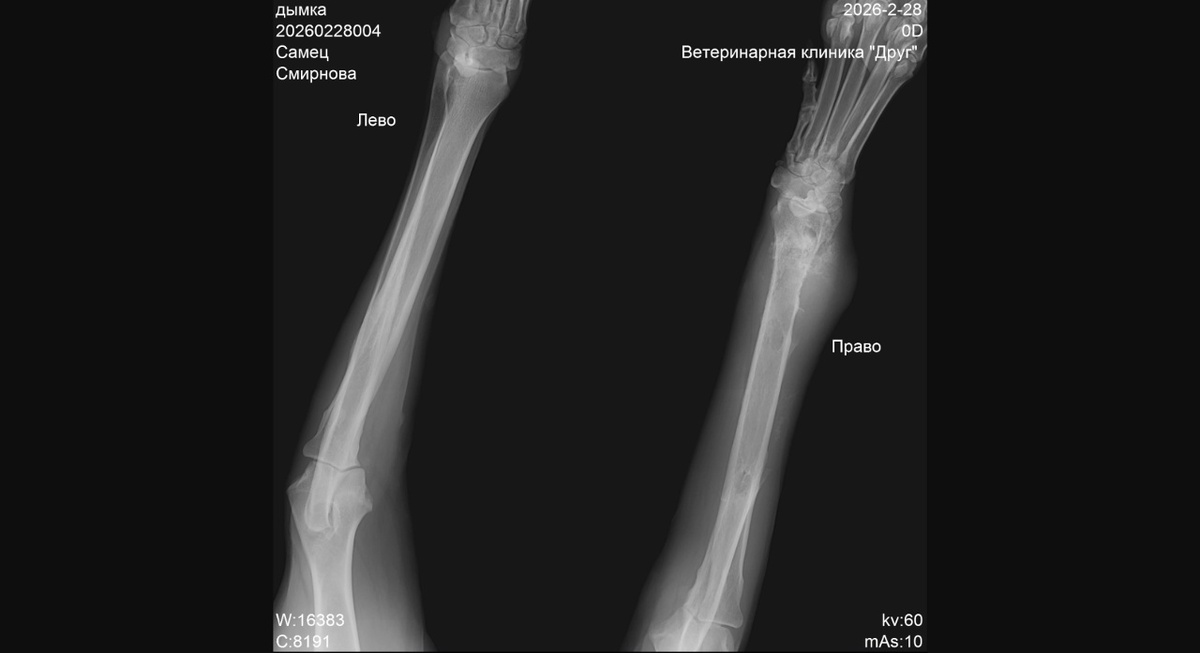

Получили Дымкин рентген и решили показать его вам.

Ну я не вижу растворившейся кости в суставе - опухший сустав вполне даже не плохо рассматривается. Честно говоря, думала что будет видно гораздо хуже из за опухлости. Но мы не врачи и в рентгене не понимаем, но предварительно все не хорошо

Рентген показали онкологу.

Онколог приглашает на прием. Онколог сразу уточнила что диагноз в назначении предварительный, предполагаемый! Врач предлагает сделать биопсию кости для подтверждения или уточнения диагноза и разработки плана лечения или иных решений. Мало того биопсию можно сделать одновременно с КТ чтобы лишний раз не наркозить собаку.